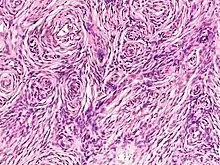

Histopathology of neurofibroma: A spindle cell lesion composed of slender fibroblast-like cells with storiform pattern and very low amount of stroma.[13]

Dermal neurofibromas may be 2 to 20 mm in diameter, is soft, flaccid, and pinkish-white, and frequently this soft small tumor can be invaginated, as if through a ring in the skin by pressure with the finger, a maneuver called "button-holing".[14]:619